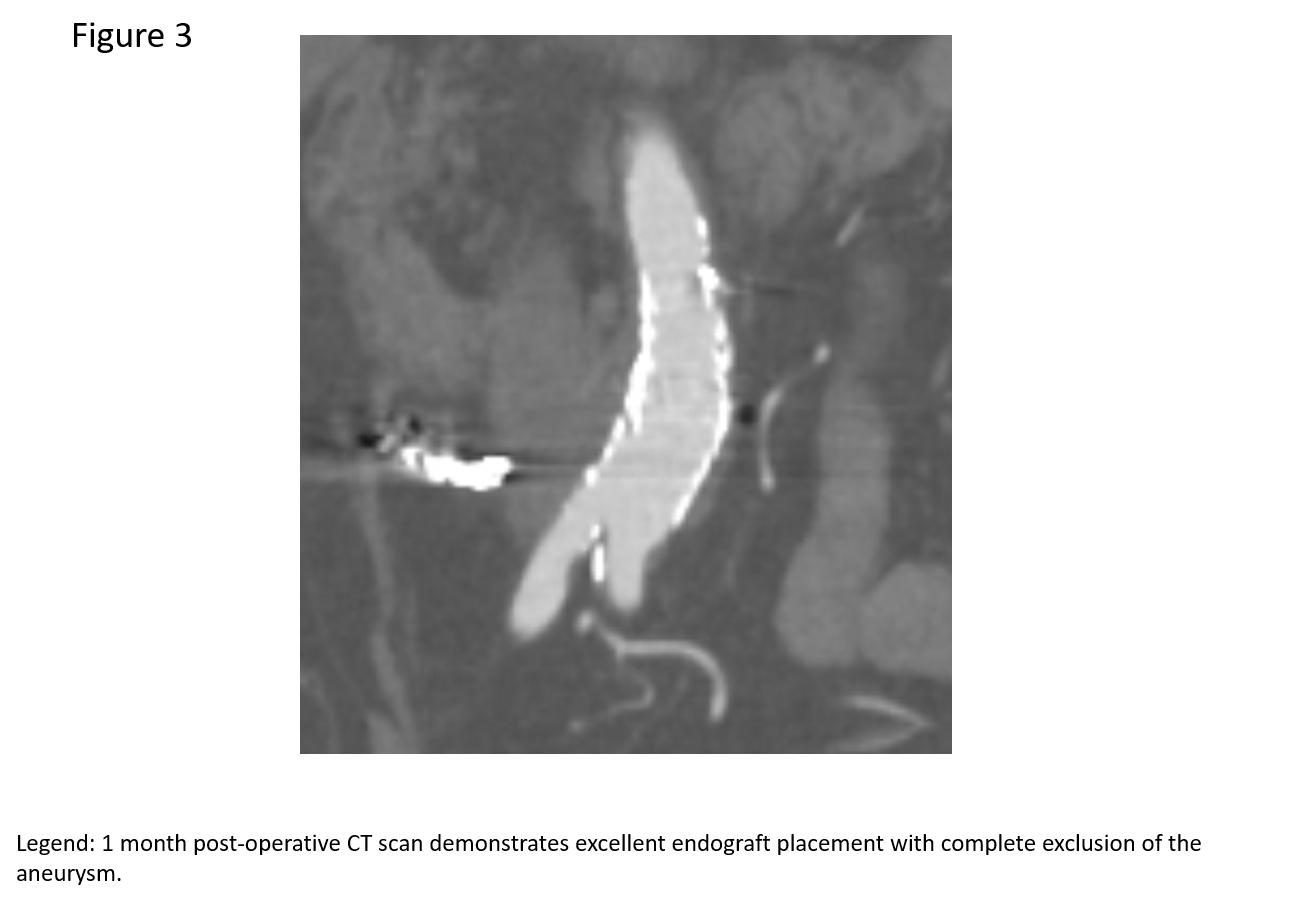

The patient was brought her to the hybridangiography suite. After obtaining femoral arterial access, a selective catheter was used to access the outflow of the pseudoaneurysm, and subsequently coil embolized it. (Figure 2a). This maneuver was designed to prevent retrograde flow into the pseudoaneurysm from the kidney.The aneurysm was excluded from the aorta by placing aortic covered stent grafts to ensure that there was no antegrade flow into the pseudoaneurysm. Completion images demonstrated exclusion of the pseduoaneurysm and preserved flow to the bilateral lower extremities (Figure 2b).The patient tolerated the procedure well. She was discharged home the next day. Follow-up CT scan at one month showed that the graft was in good position without any endoleaks; the bilateral iliac arteries were widely patent (Figure 3).